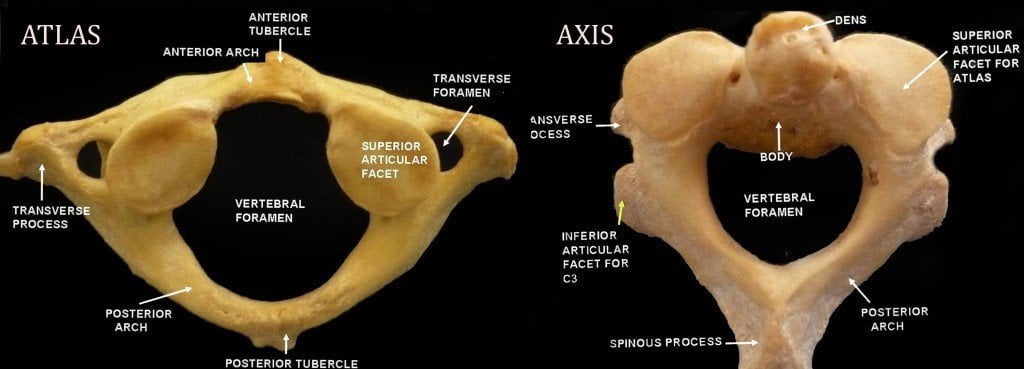

C1 is called the atlas. It has this name because it bears the skull, considered the “globe” of the body. The atlas lacks a body and bears a ring-like structure. It has a wide vertebral foramen to accommodate the thick part of the spinal cord.

Below this is the C2, called the axis. This acts as a pivot upon which the atlas rotates. The most notable part of this bone is the odontoid process, which rises perpendicularly. It is this part that breaks during a ‘judicial hanging’, hitting the medulla and causing death.